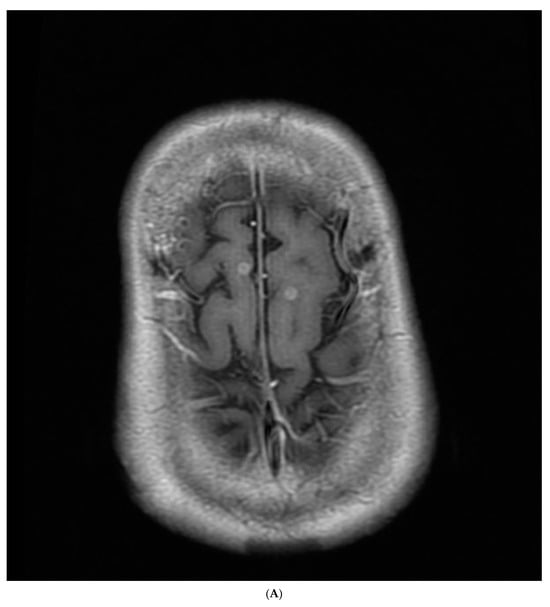

The chest radiography showed a massive right-sided pleural effusion (Figure 1A). Percutaneous catheter drainage was performed for the right-sided pleural effusion. The chest computed tomography showed a 3.3 cm × 3.0 cm mass in the right upper lobe (Figure 1B). The positron emission tomography/computed tomography revealed metastases in the left-sided supraclavicular lymph nodes, multiple bilateral mediastinal lymph nodes, and left scapula (Figure 2). The magnetic resonance imaging of the brain revealed multiple tiny cerebral and right cerebellar metastases (Figure 3). A percutaneous needle biopsy confirmed the diagnosis of lung adenocarcinoma (pT2aN3M1c, stage IVB); the analysis of the right-sided pleural effusion revealed metastatic adenocarcinoma. The genetic analysis revealed an exon 19 deletion in the EGFR gene. The laboratory tests, including the blood cell counts and chemistry, were within the normal ranges prior to treatment initiation. The patient was administered the EGFR-TKI afatinib (40 mg/day) as a first-line chemotherapy.

Figure 3.

Magnetic resonance imaging of the brain revealed (A,B) multiple tiny cerebral and (C) right cerebellar metastases.